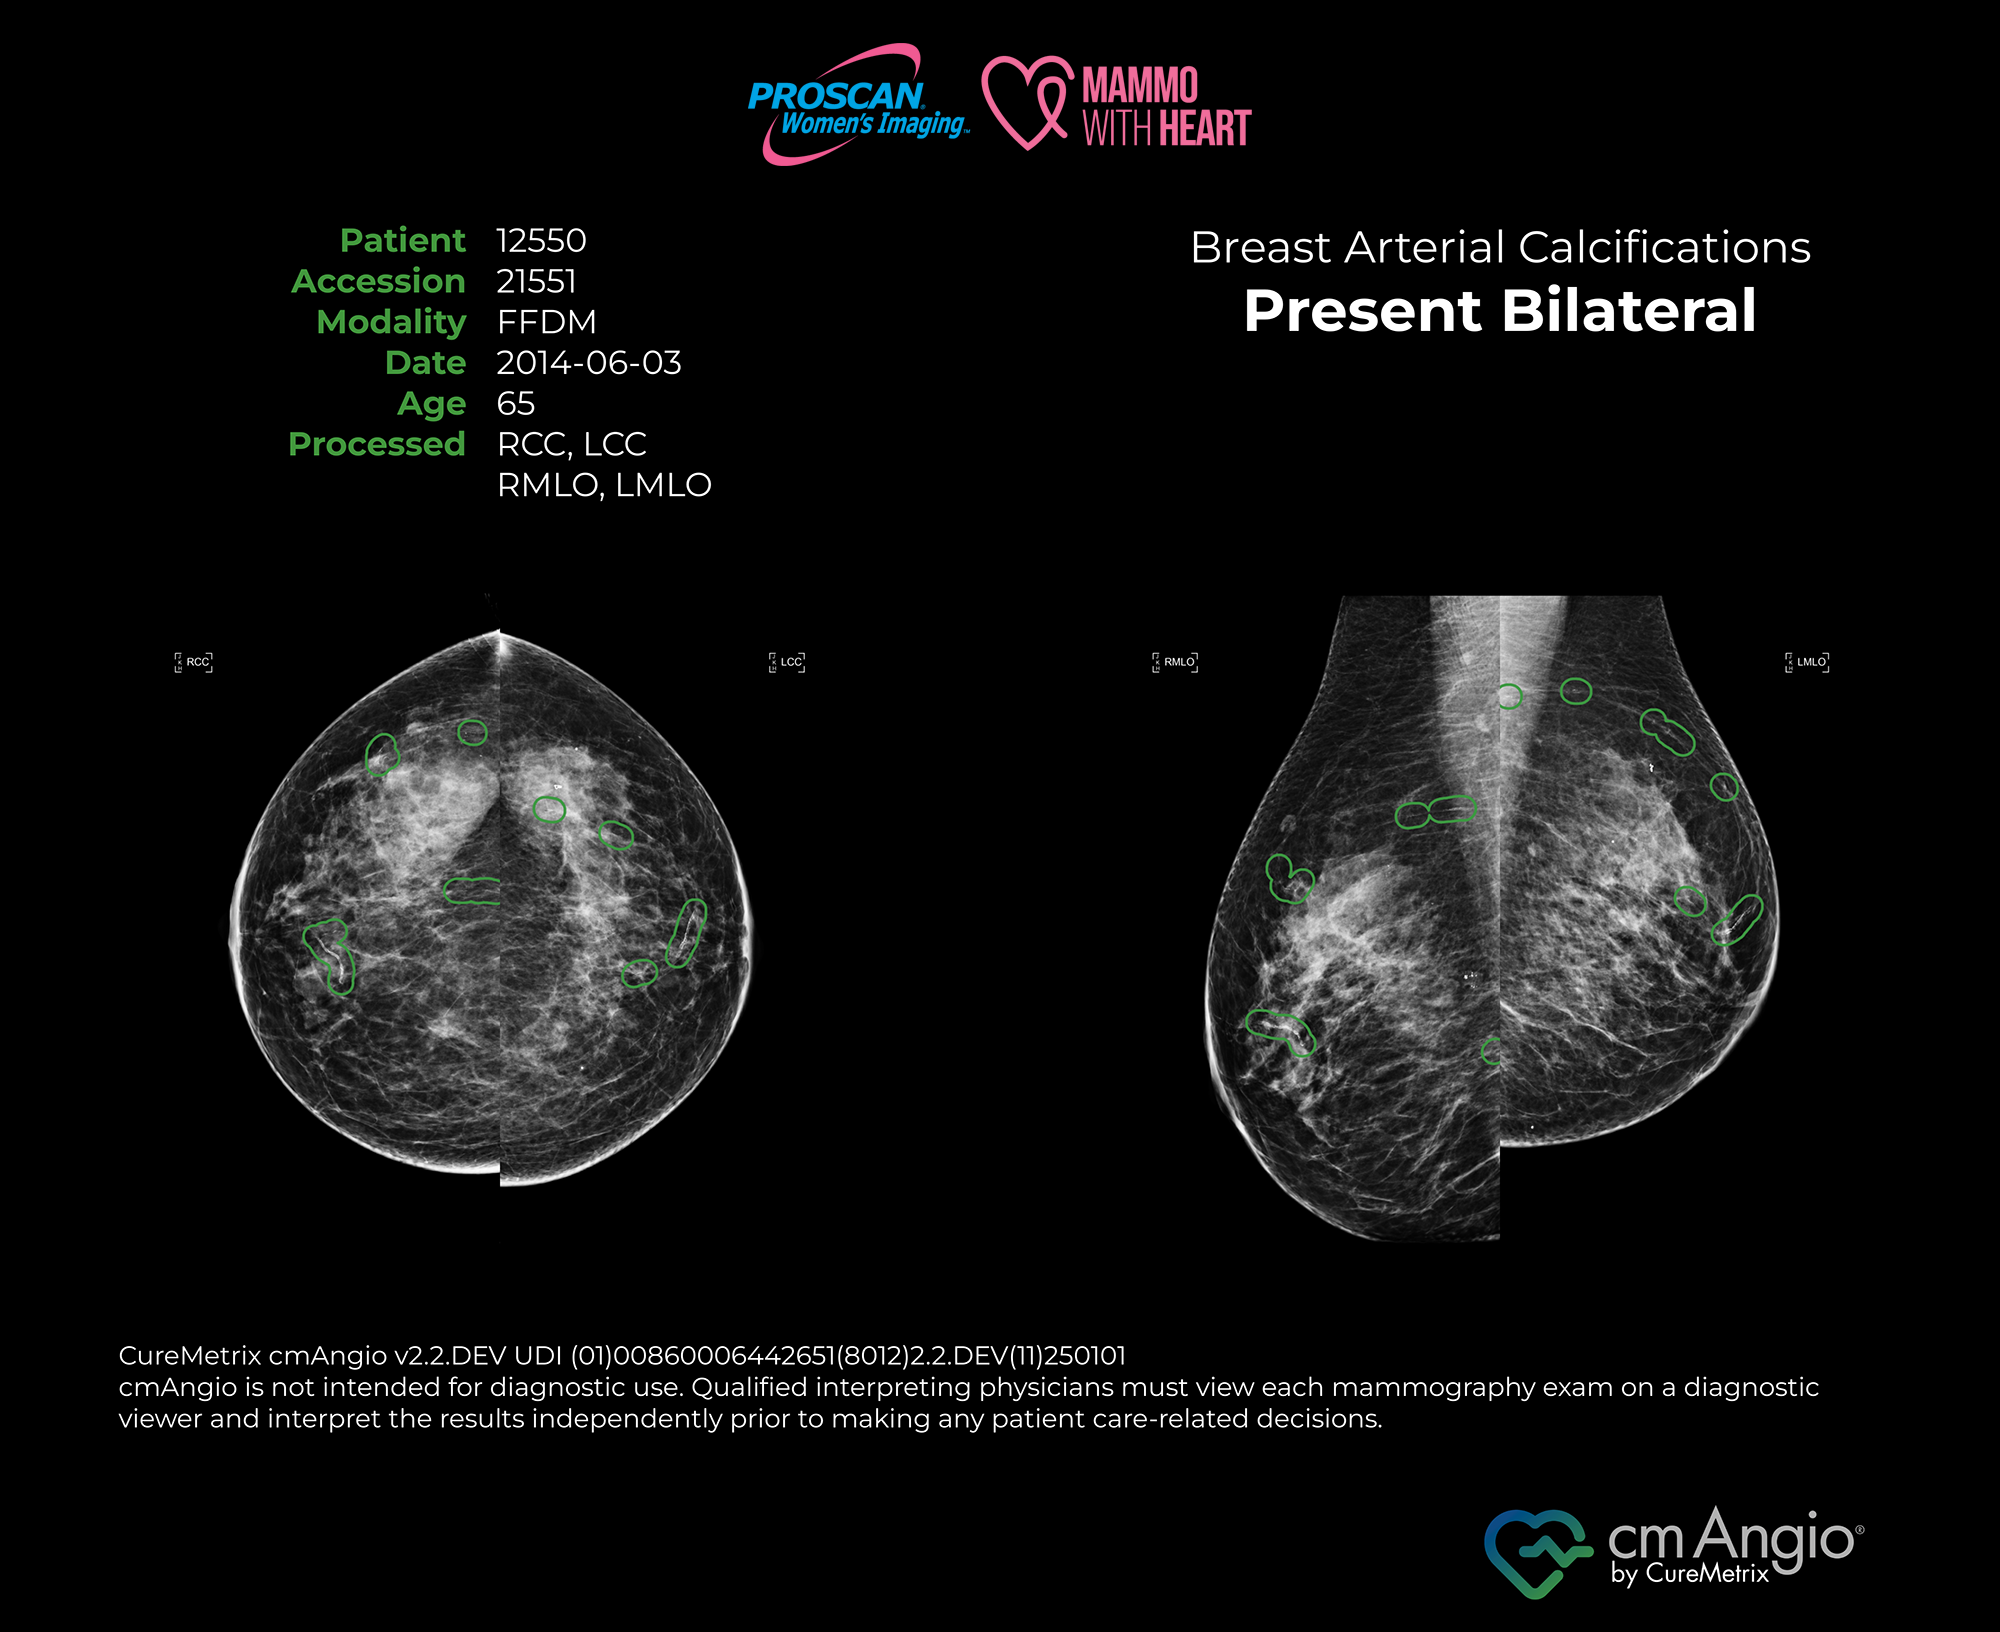

Mammo with Heart uses an FDA-cleared AI screening tool to detect signs of breast arterial calcifications (BAC) during routine mammograms — offering valuable insights into heart health without any extra scans or appointments.

Mammo with Heart utilizes cmAngio®, an FDA-cleared artificial intelligence (AI) detection software, to determine the presence or absence of breast arterial calcification (BAC) as an incidental finding in standard-view screening mammograms. The cmAngio® software is not FDA-cleared for use with screening mammograms that require displacement or alternative views; therefore, Mammo with Heart is not available to patients who need alternative views for their screening. The detection of BAC indicates calcium buildup within the breast arterial wall. While BAC has been associated with an increased risk of coronary heart and cardiovascular disease, its presence or absence does not constitute a diagnosis and should not be used alone to determine cardiovascular risk. Results from Mammo with Heart may support further clinical evaluation or patient management at the discretion of a primary care physician, cardiologist, or other specialist. If BAC is detected, please consult your healthcare provider for additional information, assessment, or treatment options.